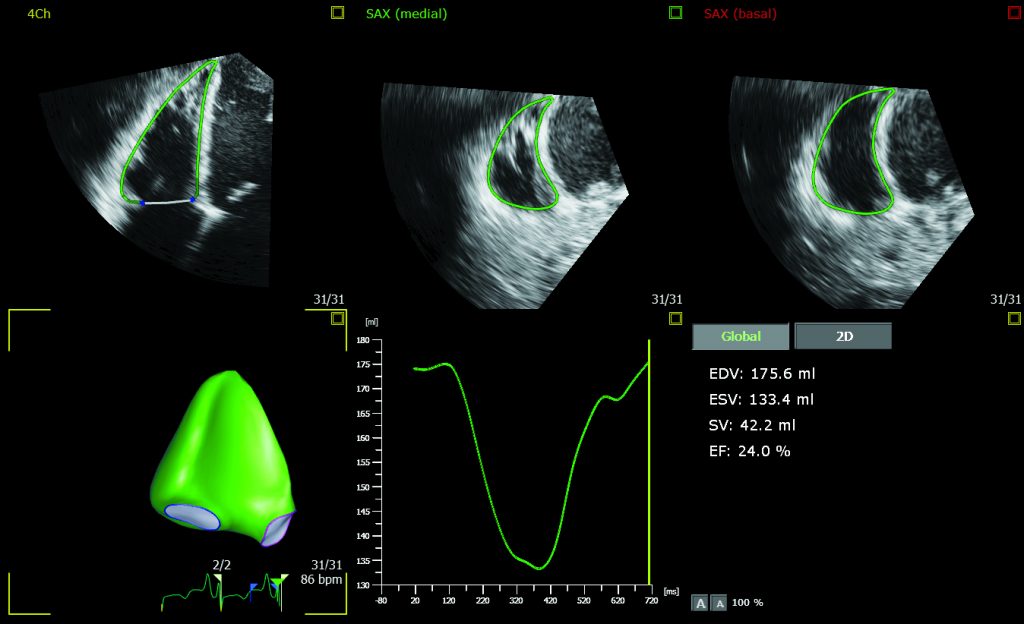

Philips EPIQ CVx — це ультразвукова діагностична система преміум-класу, спеціально розроблена для кардіологічних досліджень. Вона забезпечує високу якість візуалізації, потужні можливості обробки даних та автоматизовані інструменти для кількісного аналізу. Завдяки технології TrueVue, система пропонує фотореалістичну 3D-візуалізацію, що покращує взаємодію між медичними працівниками.

• Технології: TrueVue для фотореалістичної ехографії, Auto Measure AI для автоматизованих вимірювань, Dynamic HeartModel для 3D-аналізу серця.